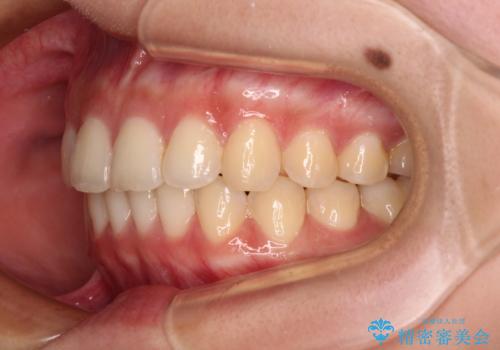

八重歯の抜歯矯正 補助装置とワイヤーを併用したインビザライン矯正治療

- 八重歯と上顎正中のズレを気にして来院された患者様です。

インビザラインによる矯正治療を希望されたため、八重歯改善のための抜歯矯正部分や上顎正中の大幅に位置移動は、補助装置やワイヤー矯正を併用し、その後はインビザラインにて行うこととしました。

骨格的に下顎が左側に変位していたため、上下正中を合わせることは困難であることは分かっていましたが、可能な限り合わせることができました。

骨格的なズレがあると仕上げの段階で奥歯の咬み合わせが不安定となるため、予定よりやや長期間となりました。